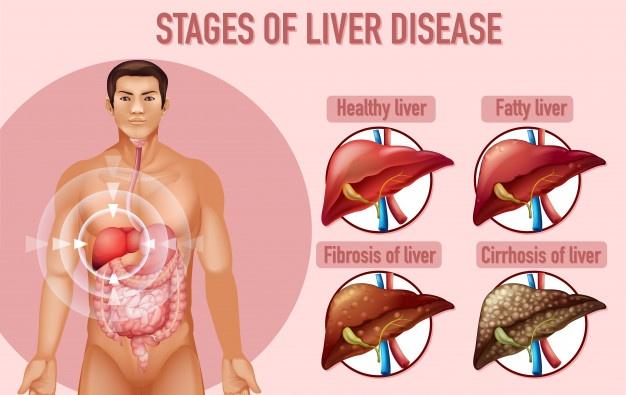

- suffer from certain medical conditions, such as hepatitis, liver cirrhosis, gallstones, diabetes, a parasite in the liver (liver flukes), and HIV